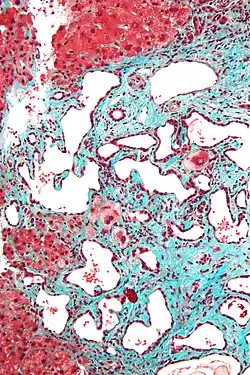

Micrograph of a bile duct hamartoma. Trichrome stain, high magnification

-